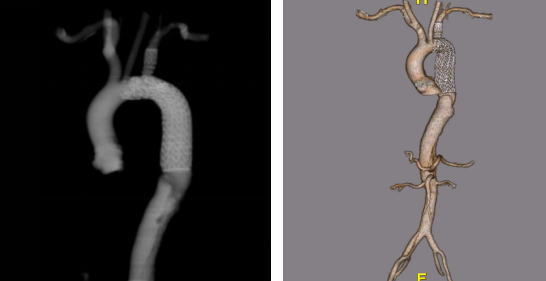

主动脉弓部病变,尤其是合并夹层、溃疡或壁间血肿时,一直是血管外科手术中的难点与高危区域。传统开放手术虽能彻底重建,但创伤大、死亡率与神经系统并发症发生率高。近年来,腔内修复技术(TEVAR)逐步向弓部延伸,医生自制改装支架与新兴商业支架并行发展,为这一领域带来新的可能性。

山西医科大学第二医院血管外科团队积累了丰富的弓部腔内修复经验。本文结合其近期学术报告与病例资料,系统梳理自制开窗支架与商业分支支架在弓部修复中的应用现状、技术要点与未来展望。

自制改装支架:两种开窗技术的实战应用

自制改装支架(Physician-Modified Stent Graft)是当前许多中心开展弓部修复的务实选择。团队主要采用两种技术:

(一)原位开窗(In-Situ Fenestration)

★ 病例1

73岁男性,主动脉夹层合并壁间血肿,心肺功能差,无法耐受开放手术。

(二)体外开窗(Ex-Vivo Fenestration)

★ 病例2

41岁男性,主动脉夹层,弓部锚定区极短。